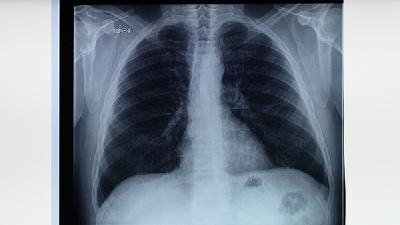

什么是小细胞肺癌